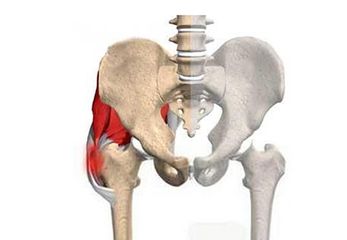

股骨头坏死是一个病理演变过程,初始发生在股骨头的负重区,应力作用下坏死骨的骨小梁结构发生损伤即显微骨折以及随后针对损伤骨组织的修复过程。

股骨头坏死病因不外有两种:一种发生在股骨颈骨折复位不良的愈合,股骨头内的负重骨小梁转向负重区承载应力减低,出现应力损伤,所以坏死总是发生在患者骨折愈合,负重行走之后。另一种是骨组织自身病变,如最常见的慢性酒精中毒或使用糖皮质激素引起的骨坏死,同时骨组织的再生修复能力障碍。此外还包括儿童发育成长期股骨头生发中心-股骨头骨骺坏死,又称儿童股骨头坏死,扁平髋。